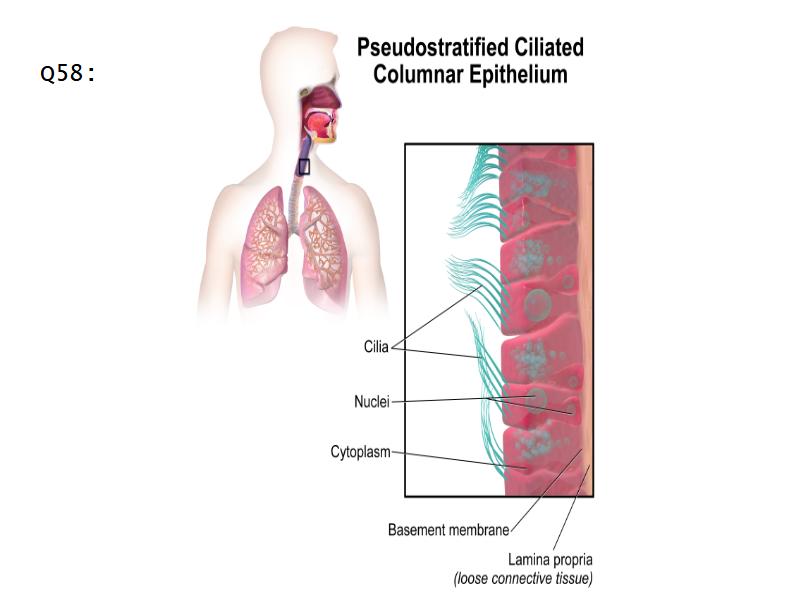

Respiratory epithelium

- Pseudostratified

- Ciliated

- Columnar

- Epithelium with

- 4 Cells

- Ciliated columnar cells

- Non-ciliated columnar cells

- Goblet cells

- Basal cells